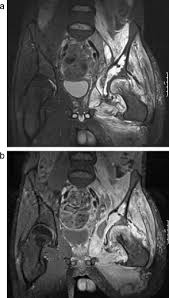

What Are The Symptoms Of Pelvic Bone Cancer : Surgical Management Of Pelvic Primary Bone Tumors Involving The Sacroiliac Joint Sciencedirect - Bone cancer destroys normal bone tissue.. More rarely, the base of the skull is affected. Chondrosarcoma is a cancer that can begin in the bones or tissue near bones, often in the hip, pelvis, and shoulder. Symptoms if cancer has spread to the lymph nodes lymph nodes are part of a system of tubes and glands in the body that filters body fluids and fights infection. The most common locations for chondrosarcoma tumors are in the pelvis, hip and shoulder. Rarely, people with a bone sarcoma may have symptoms such as fever, generally feeling unwell, weight loss, and anemia, which is a low level of red blood cells.

A high temperature (fever) of 38c (100.4f) or above It can spread to distant organs, such as the lungs. Bone cancer is rare, making up less than 1 percent of all cancers. Pelvic bone neoplasms are seldom immediately diagnosed and, therefore, may result in significant morbidity and mortality. Osteosarcoma is probably the most common disease that is related to pelvic bone cancer, with chondrosarcoma following close behind it. Hip pain is a common complaint like that of knee or back pain. At first, the pain is not constant. Bone metastases can weaken your bones and lead to symptoms like bone pain. The bones are the most common place where metastatic breast cancer cells tend to go. Chondrosarcoma is a cancer that can begin in the bones or tissue near bones, often in the hip, pelvis, and shoulder. Symptoms of testicular cancer may include: Can bone cancer be found early? Having too much calcium in your blood , which has numerous causes, is a dangerous condition called.

Bone cancer can begin in any bone in the body, but it most commonly affects the pelvis or the long bones in the arms and legs. There are many pelvic cancer symptoms a person can experience. Bone cancer develops in the skeletal system and destroys tissue. The symptoms of bone cancer are: In contrast, some other metastatic tumors, such as those from the prostate, are commonly osteoblastic, meaning that they form new bone and increase the brittleness of the bones. Rarely, people with a bone sarcoma may have symptoms such as fever, generally feeling unwell, weight loss, and anemia, which is a low level of red blood cells. Although breast cancer can spread to any bone, the most common sites are the ribs, spine, pelvis, and long bones in the arms and legs. Osteosarcoma is probably the most common disease that is related to pelvic bone cancer, with chondrosarcoma following close behind it. A primary bone cancer is one that starts from bone. Although less often, other areas (such as the ribs) may be affected. Can bone cancer be found early? Hip pain is a common complaint like that of knee or back pain. Get the latest health information from mayo clinic delivered to your inbox.

The bones are the most common place where metastatic breast cancer cells tend to go. A person may, for example, have lumps in the pelvic region or experience pain in the area. Learn more about the symptoms, risk factors, diagnosis, types, treatment, and outlook for bone cancer. Your red blood cell levels may drop, causing anemia. Pain, fever, and fatigue are all symptoms associated with pelvic bone cancer. Chondrosarcoma is a rare type of cancer that usually begins in the bones, but can sometimes occur in the soft tissue near bones. There's no cure for metastatic bone cancer, but treatment options may help alleviate symptoms to keep you comfortable. Pain and swelling in the. At first, the pain is not constant. Metastatic tumors of the bones are usually osteolytic, which means that they dissolve the bone and cause multiple fractures. Abstract low back pain and sciatica are usually attributed to localized structural pathology; The long bones of the body — such as the arms and legs — and the pelvis are commonly affected. Symptoms if cancer has spread to the lymph nodes lymph nodes are part of a system of tubes and glands in the body that filters body fluids and fights infection.